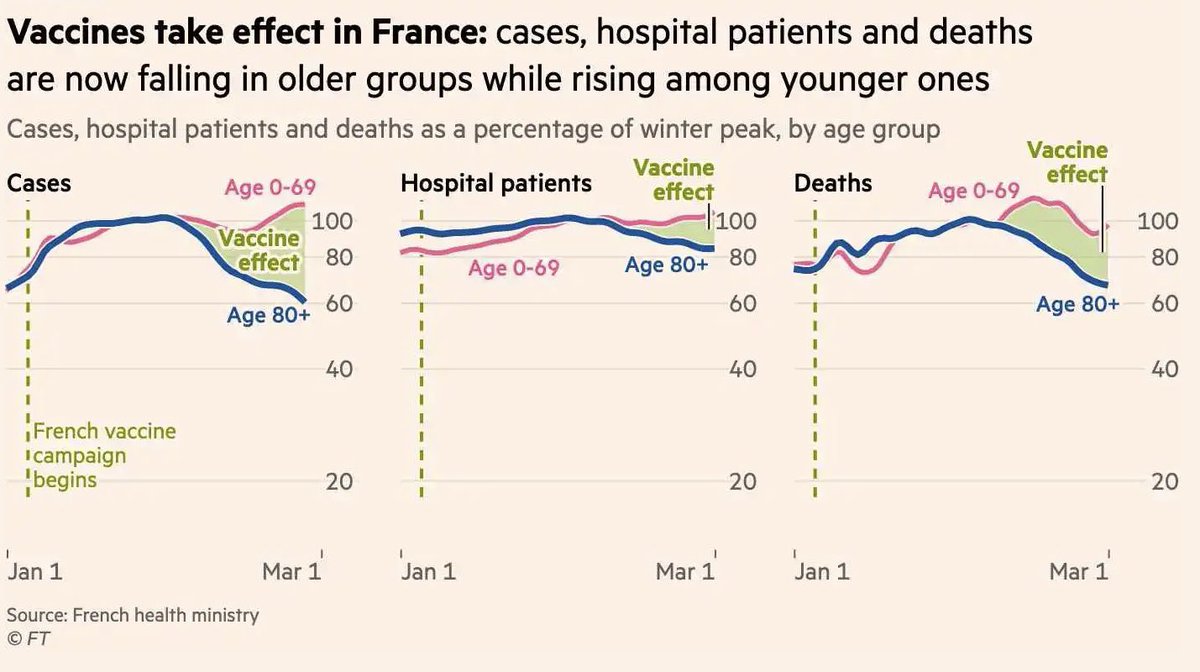

Regardez l’efficacité impressionnante des vaccins. En France, pour la 1ère fois, le nombre de cas, d’hospitalisations et de décès baisse chez les plus de 80 ans (bleu, qui sont vaccinés en priorité) alors qu’il augmente chez les 0-69 ans (rose, peu vaccinés)… Source Financial Times